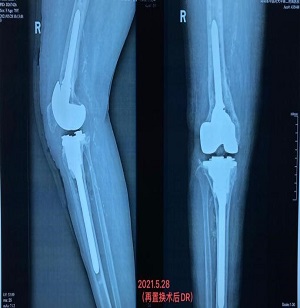

年近八旬的欧娭毑患重度膝关节骨性关节炎多年,2017年在某医院做了右侧人工全膝关节置换,但术后恢复一直不佳,关节疼痛越来越明显。2018年初又因膝关节疼痛、行走不便摔伤导致右股骨骨折。2020年7月,欧娭毑再次在家摔倒致右耻骨骨折,关节疼痛带来的诸多问题让欧娭毑和子女揪心不已。至2020年底,欧娭毑出现右膝关节红肿发热,疼痛难耐。2021年元旦一过,倍受疼痛困扰的欧娭毑由家人送至湖南省中医院关节骨病科住院治疗,经诊断为“右人工膝关节置换术后感染并假体松动”。

鉴于欧娭毑病情复杂,又年近八旬,且合并心肺等内科基础疾病较多,董克芳主任手术团队经讨论后,为欧娭毑制定了分期手术方案。1月26日,专家团队顺利为欧娭毑完成了右股骨内骨定取出术+右膝关节骨水泥旷置术。2月10日,大年三十前夕,欧娭毑顺利出院回家和家人一起过新年了。

3个月后,5月25日,按照既定手术方案,专家团队顺利为欧娭毑完成了人工全膝关节表面再置换术。目前,欧娭毑恢复良好,已在医师指导下进行下地负重及行走锻炼,医师查房时,欧娭毑忍不住感慨:“我这把年纪,实在是经不起折腾了,我来中医院住过很多回了,就相信你们中医院!”